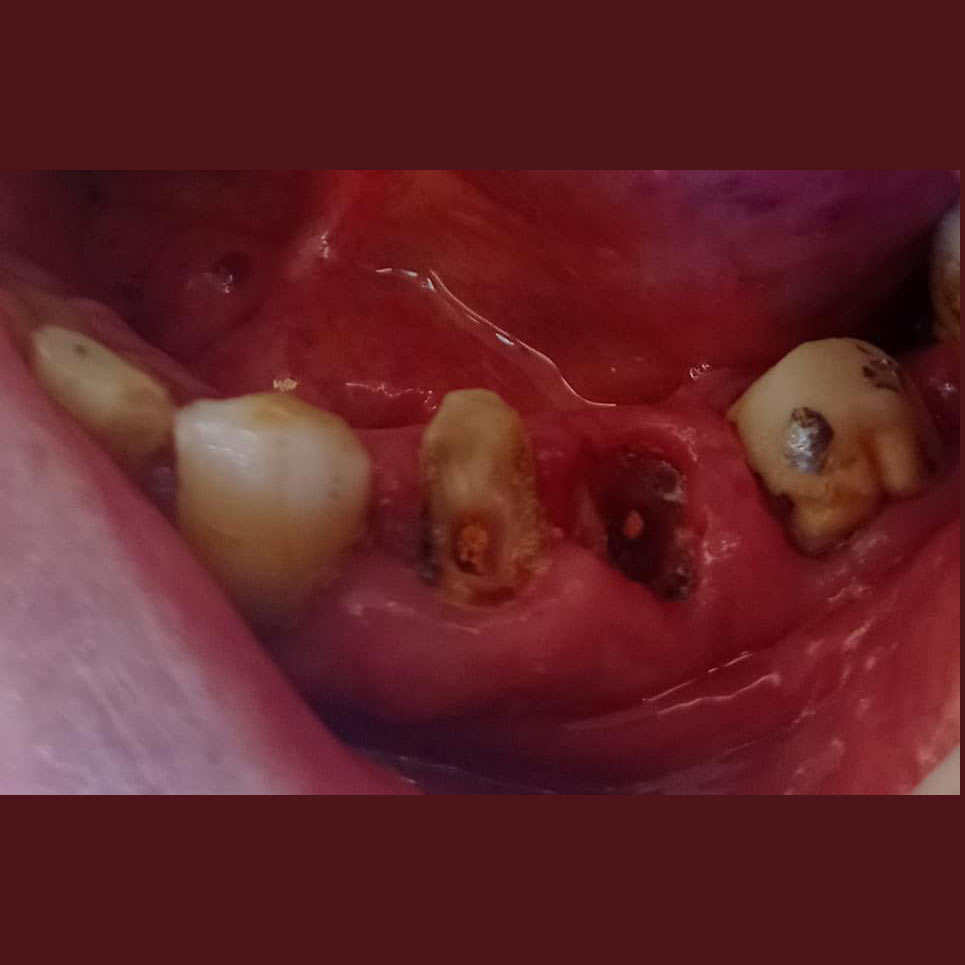

Έχετε στο στόμα σας, κενά από δόντια που έχουν χαθεί ή είναι τα δόντια αρκετά χαλασμένα, ή έχουν υποστεί φθορά ή σπασίματα ;

Με σωστή τήρηση και ευλάβεια και σεβασμό στη βιολογία, φυσιολογία και ανατομία του στόματος , ιστών , δοντιών, παρασκευάζουμε τα δόντια άρτια, όμορφα και με ευγένεια για αναπληρώσουμε τις όποιες απώλειες δοντιών, καταστροφές, φθορές και φυσικά αισθητικές ανάγκες.